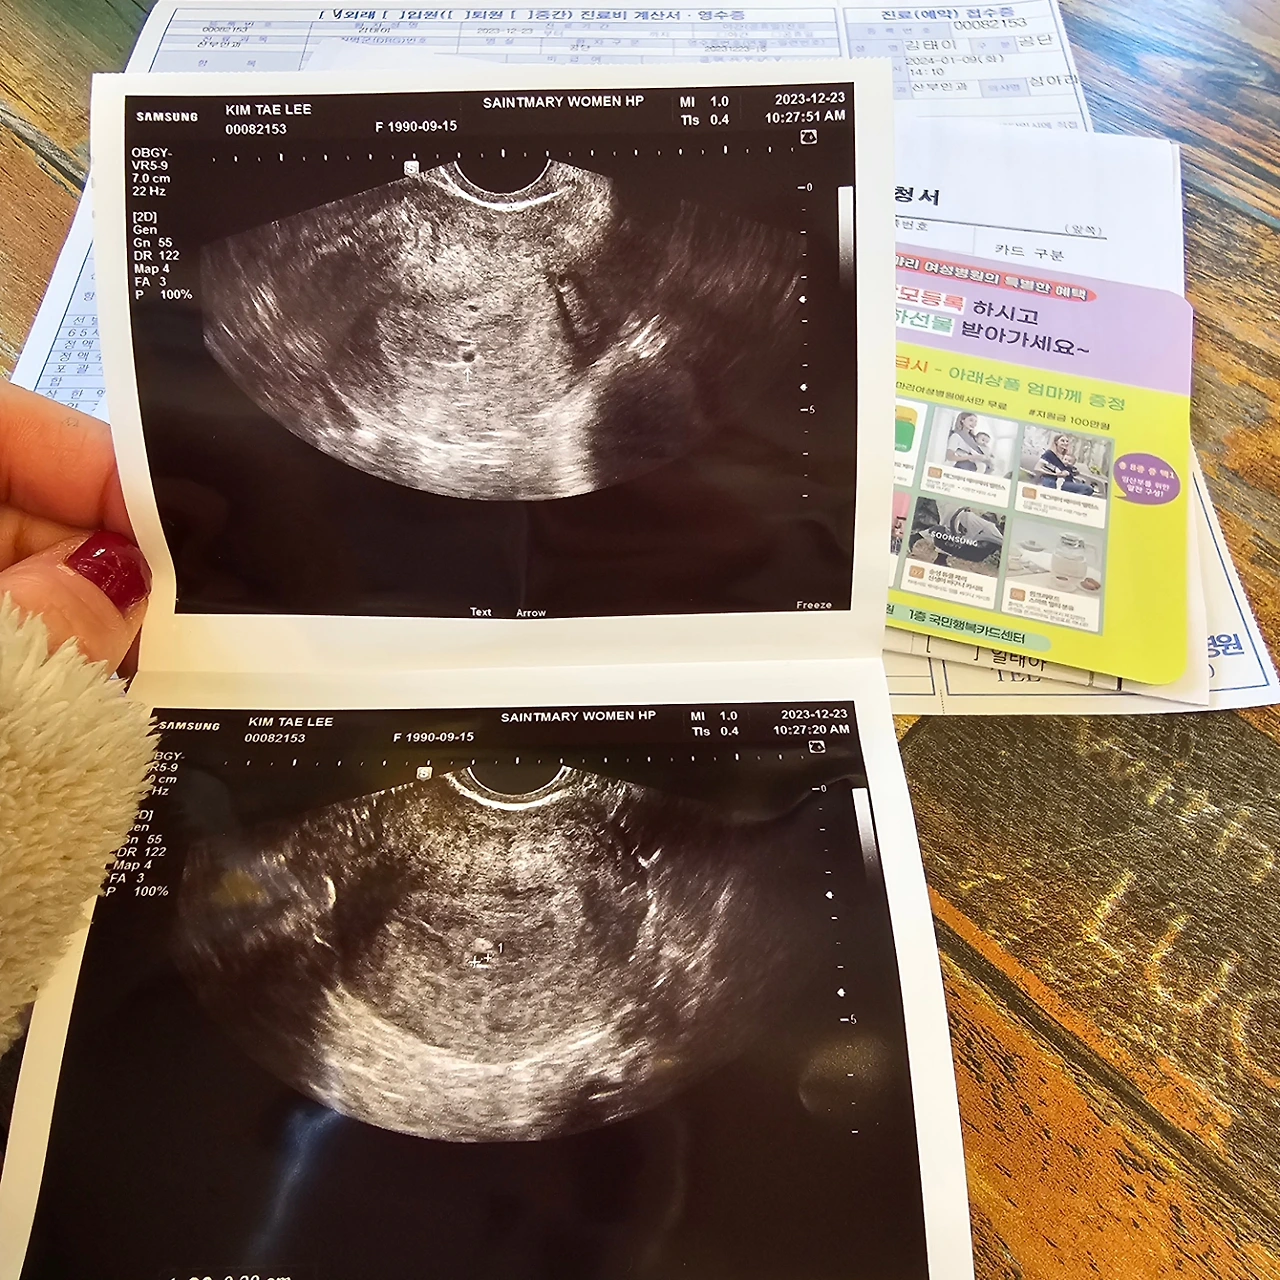

아침 아홉시에 진료를 시작하는 세인트마리 산부인과는 난임과 시험관 등으로 유명한 11명의 전문의가 있는 대형병원이다.

우리는 아침을 먹고 9시 6분쯤 도착했는데 이미 주차는 만차였고 근처에 있는 다른 건물에 주차를 했다.

대기실은 발딛을 틈 없이 산모들과 보호자들로 가득차 있었고, 저출산시대라는 미디어의 말이 무색할 정도로 여기저기 배불뚝이 산모들이 걸어다니고 있었다.

우리는 번호표를 받고 1시간 40분을 기다려 내 담당 의사쌤을 만날 수 있었다.

의사: 네 무슨 일로 오셨죠?

나: 임테키가 두줄.....

의사: 하하하하 좋은 일이네요, 일단 초음파를 한번 봅시다.

초음파 결과 콩알만한 아기집이 형성되어 있었고 나는 임신 4주차라고 했다.

얼마 전 맞았던 생리 유도주사의 경우, 임산부에게는 자궁을 튼튼하게 해주는 역할을 해서 오히러 유산을 방지하기 위해 필수적으로 맞아야하는 주사로 쓰이기도 한다고 했다.

결론적으로, 나는 임산부가 맞았고 오빠는 하룻밤새 남친에서 예비아빠 신분으로 변해있었다.